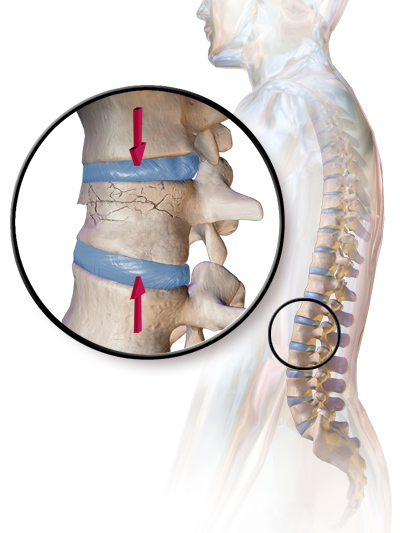

- 압박 골절/쐐기 골절 – 보통 척추에서 발생하며, 예를 들어 척추뼈의 앞부분이 골다공증으로 인해 무너지는 경우(외상 유무에 관계없이 뼈가 부서지기 쉽고 골절되기 쉬운 의학적 상태)

- 압박 골절(흉추 및 요추)

- 분쇄 또는 파열 골절(흉추 및 요추, 챈스 골절)

- 척추 압박 골절